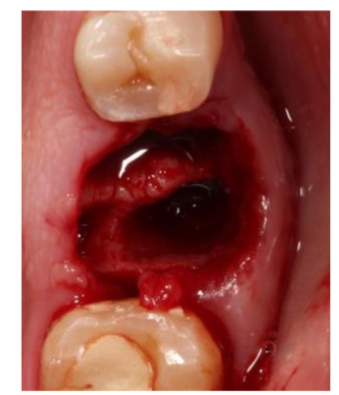

Described here is one case our of 20, wherein a healthy male patient without any medical condition, reported at the dental office with fractured lower mandibular first molar (#36). A treatment plan of socket preservation and implant placement was given to him to which he readily agreed. Minimally invasive tooth extraction was done under local anesthesia and care was taken not to damage either of the bony walls.

After extraction, the socket was not compressed so that the width of the ridge is maintained. Maxresorb bone graft (Botiss, Germany) was placed in the socket.

A single layer of collagen membrane, Ossix plus membrane (Dentsply Sirona, Germany) was placed on the bone graft and 3-0 silk sutures were placed in a manner to hold the tissue and membrane in place however no attempt was made to approximate the open ends of soft tissue. It should also be noted that in such cases achieving primary closure is not possible unless the mucoperiosteum flap is not mobilized.